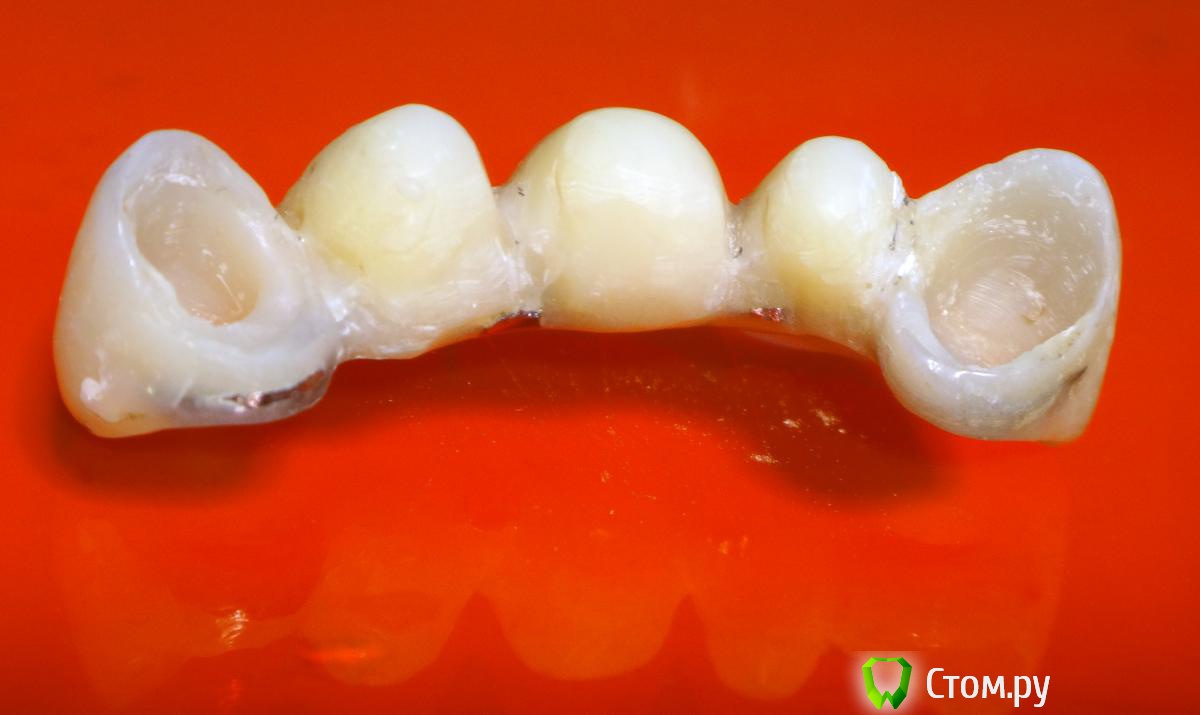

Kalipso Опубликовано 28 августа, 2014 Поделиться Опубликовано 28 августа, 2014 Я ставлю сразу после удаления .1 . Снимаю слепок до удаления , и прошу техника либо сделать коронку или wax up после чего по ключу сама изготавливаю .2. Удаляю .3.Жидкотекучим креплю коронку . Как- то так . Это наверно самая моя первая такая работа .http://s017.radikal.ru/i432/1408/7c/d61e22c1c7ae.jpg http://s018.radikal.ru/i519/1408/d2/23c0aebcd1b4.jpg http://s016.radikal.ru/i336/1408/51/3ede7c77a5d0.jpg http://s41.radikal.ru/i091/1408/cc/604419754cb7.jpg 3 Ссылка на комментарий

Slaggy Опубликовано 11 сентября, 2014 Поделиться Опубликовано 11 сентября, 2014 (изменено) Если планируется удаление переднего зуба, то стараемся одномоментно установить имплантат. Если это невозможно или нельзя нагружать винт, то делаем адгезивный "мериленд". Если пролёт в несколько зубов, то только съёмное. Можно дополню?Если пролет в несколько зубов, но ограничивающие деффект зубы будут обтачиваться, то можно армировать времянки металлом.вторую фотку перезагружаю:Это как раз на 3-4 день овоиды сделаны. первая фотка на 3-4 день после 3-4 дня после удаления.Что скажите мне изменится в поверхностных слоях сгустка и окружающих их тканей за 3-7 дней? Прорастет чем? или что?Нифига не вижу разницы одномоментно или на 3 день. Ааа. Есть разница. Не кровит и можно работать.А еще пациент осознав потерю значимей оценит обретение. Если удаляемый зуб имеет коронку, то можно его использовать для времянки.Извините за качество, не успел отфоткать - фотик сдох, успел пару раз нажать на затвор без подготовки.Вся центральная группа с клиновидными деффектами и подвижна, 21 - выдвинут на 3,5 мм. пациент не хочет с ним расстоваться, держит губами, оберегает.Нужен был быстрый "ход конем", чтоб он на шею не сел. Я пообещал за час сделать лучше чем есть. Пальцами удалил 21, обрезал под овоид, ретроградно запломбировал жидкотекучим, им же залил клиновидный и приклеил, армировав стекловолоконной лентой.Говенная работа, но она позволит мне дальше человека вывести на нормальное лечение.Вообще данный товрисч очень тяжелый, там все под бульдозер, а потом...Еще рас сорри за жесть, но это жизнь, работа, будни ))))) Изменено 11 сентября, 2014 пользователем Slaggy Ссылка на комментарий